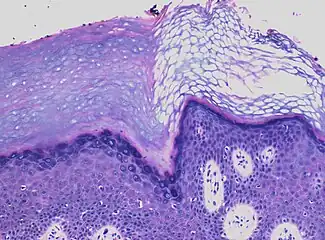

a) Focal parakeratosis b,c) prominent parakeratosis

In contrast, hyperkeratosis (pictured) may also show a heterogeneous stratum corneum, but a preserved granular layer is seen.